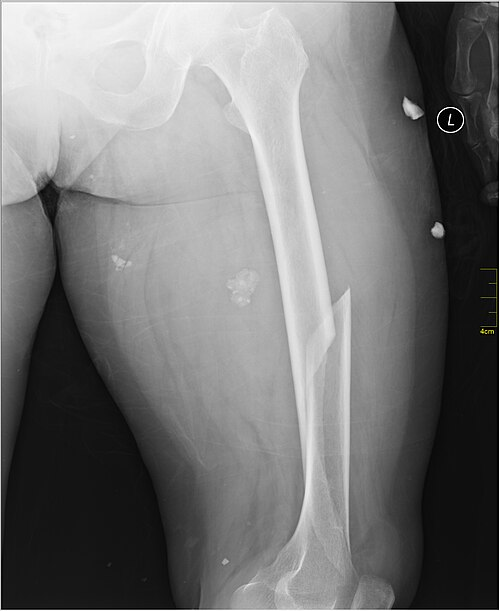

بهترين درمان شکستگی تنه استخوان ران در بالغین

بهترین و استانداردترین روش درمانی برای شکستگی تنه استخوان ران در بالغین، عمل جراحی «میله‌گذاری داخل مغز استخوان قفل شونده» (Intramedullary Nailing – IMN) است. اما انتخاب بهترین رویکرد جراحی نیازمند مشورت با یک متخصص زبده است، به ویژه اگر به دنبال دکتر ارتوپد مشهد با تجربه در این حوزه باشید. این روش به دلیل ایجاد پایداری قوی، کمترین آسیب به بافت نرم اطراف و فراهم کردن شرایطی برای شروع زودهنگام حرکت و راه رفتن، نتایج بالینی برتری نسبت به سایر روش‌ها دارد. در ادامه این مقاله به بررسی روش‌های درمانی شکستگی تنه استخوان ران در افراد بالغ خواهیم پرداخت.

به دلیل نیروی زیاد لازم برای شکستن استخوان ران، این آسیب تقریباً همیشه با جابجایی قطعات همراه است و درمان‌های غیر جراحی (مثل گچ گرفتن) ناکارآمد بوده و منجر به جوش خوردگی نامناسب می‌شوند. در نتیجه جراحی با میله داخل استخوانی (IMN) در اغلب موارد به عنوان بهترین و استانداردترین روش درمانی انتخاب می‌شود.

در این روش، یک میله فلزی توخالی (معمولاً از جنس تیتانیوم) از طریق یک برش کوچک وارد کانال استخوانی شده و با پیچ‌های قفل شونده قطعات را تثبیت می‌کند. مزایای اصلی IMN شامل ایجاد پایداری مکانیکی بالا، حفظ خون‌رسانی برای جوش خوردن سریع‌تر و امکان شروع سریع‌تر وزن گذاری نسبی برای بیمار است که به کاهش عوارض جدی پس از عمل (مانند آمبولی چربی) کمک می‌کند.